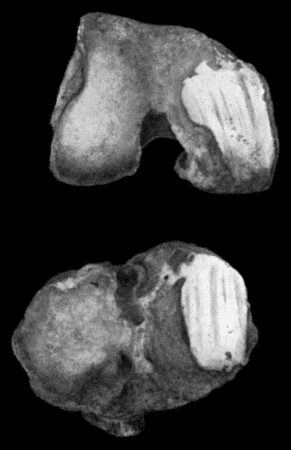

118.Shaft of the Femur after Acute Osteomyelitis 444

119.Femur and Tibia showing results of Acute Osteomyelitis 445